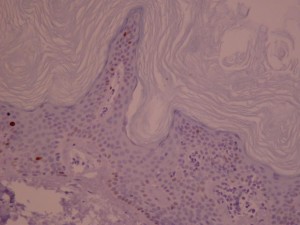

Ki-67 staining of an acantho-hyperkeratotic type of SK. On the last picture, most of the basal staining comes from the accumulation of pigment as the clinical image suggests.

Ki-67 staining of an acantho-hyperkeratotic type of SK. On the last picture, most of the basal staining comes from the accumulation of pigment as the clinical image suggests.

Ki-67 staining of an acantho-hyperkeratotic type of SK. On the last histological picture, most of the basal staining comes from the accumulation of pigment as the clinical image suggests.